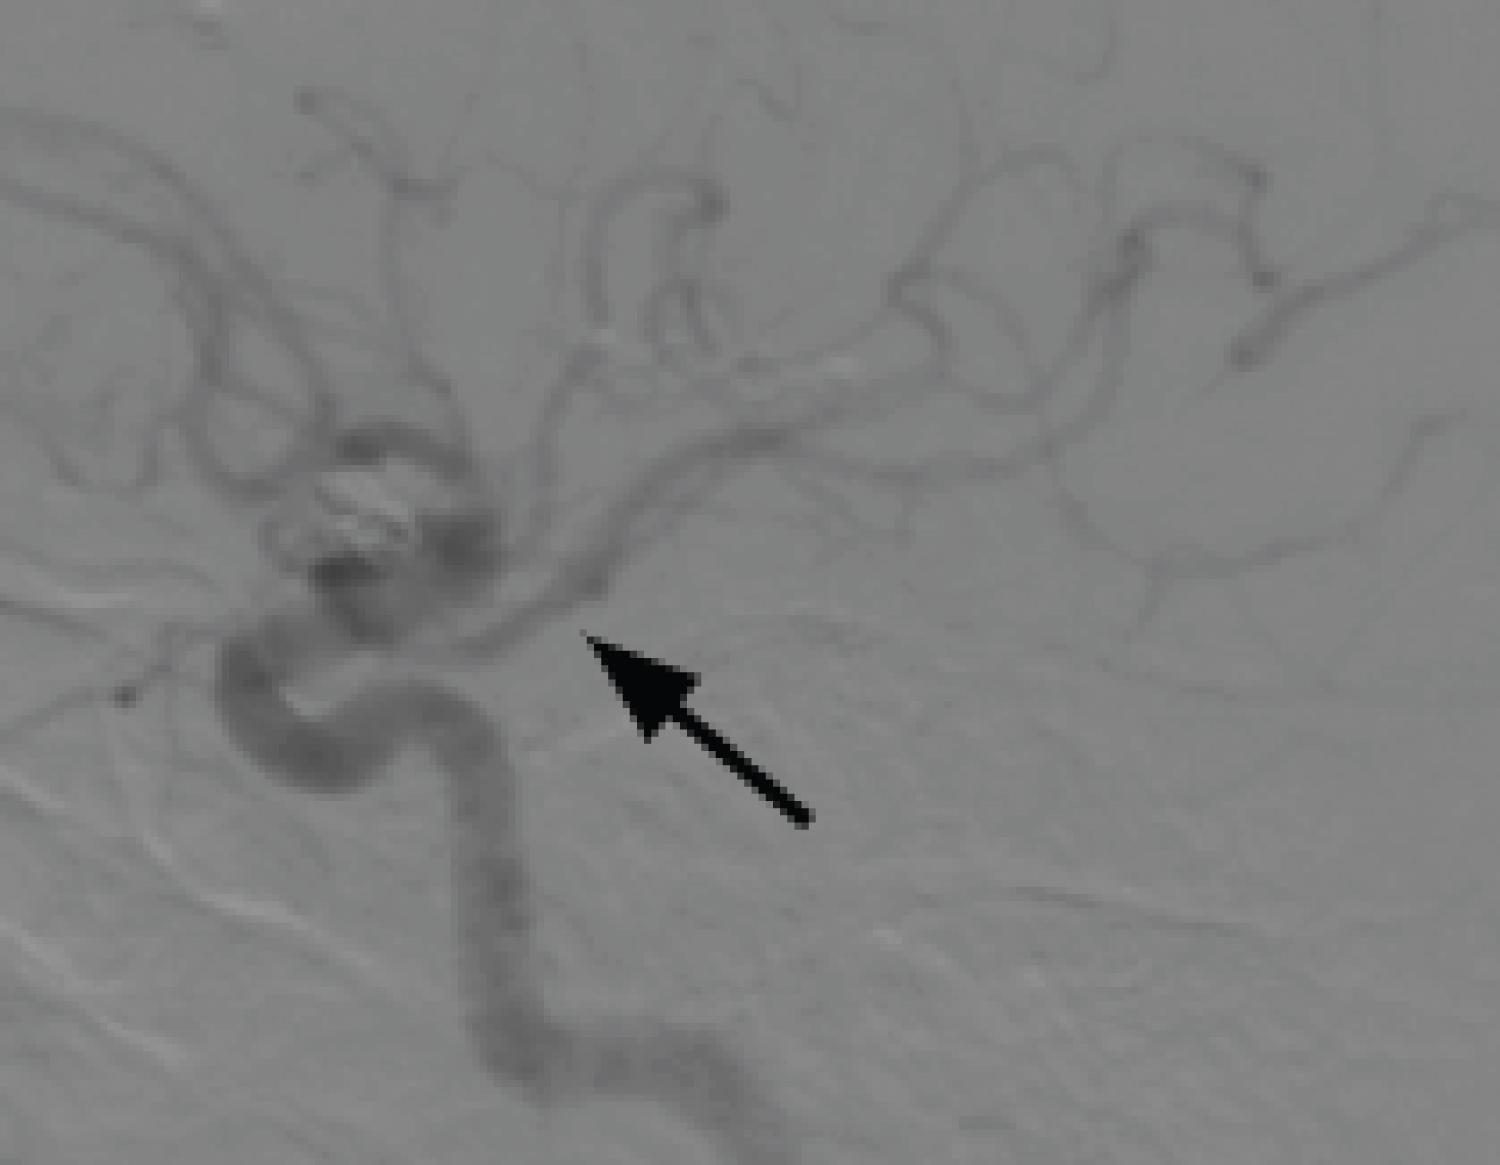

The diagnostic workup was extended with cerebral arteriography, during which the trident sign (Figure 2) compatible with Persistent Trigeminal Artery was observed, along with the absence of the right posterior communicating artery (P-com), classifying the Persistent Primitive Trigeminal Artery as type I of Saltzman. The left P-com originates from fetal circulation (Figure 3), while the right vertebral artery terminates in the right Posterior Inferior Cerebellar Artery (PICA), and the left vertebral artery is dominant (Figure 4).

Figure 3: Profile view of left internal carotid artery arteriography (ACIE), arterial phase, black arrow indicating fetal-type left posterior communicating artery (P-com). View Figure 3